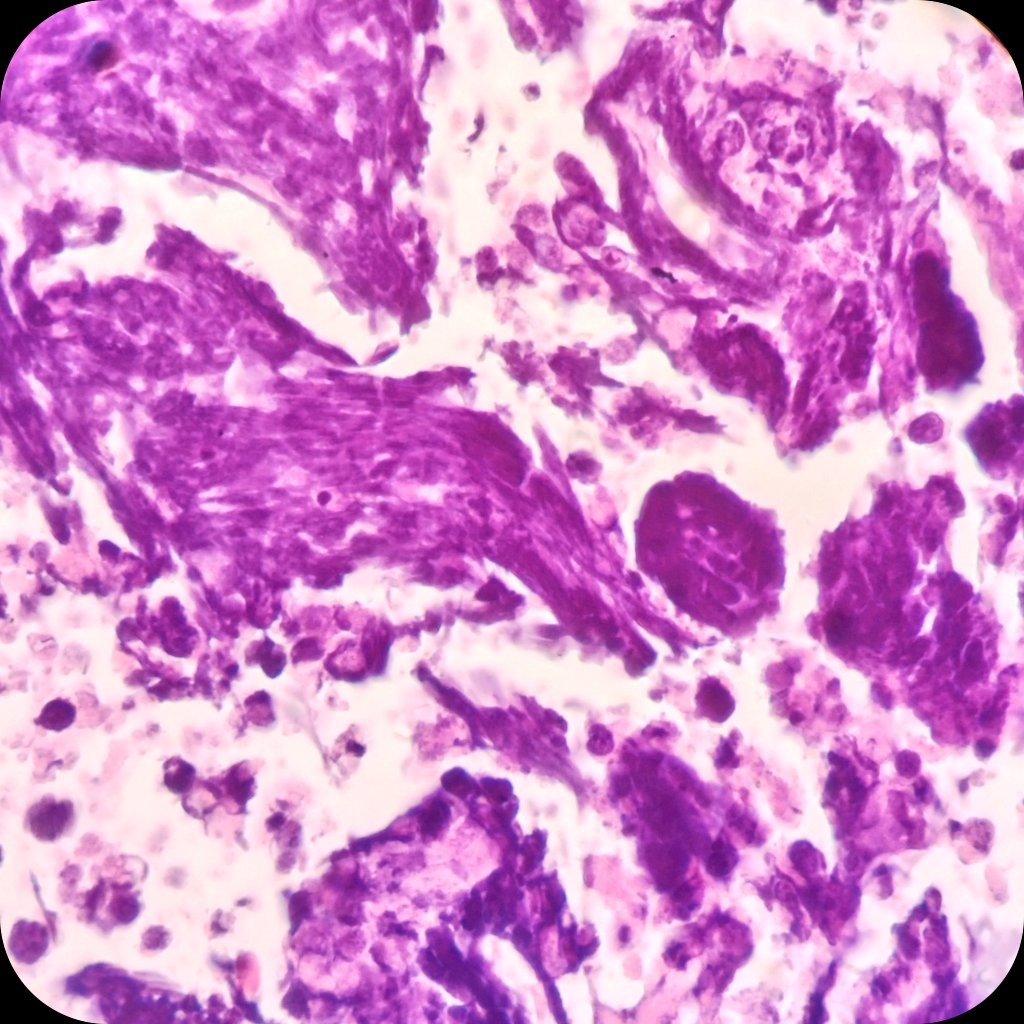

🧱 ΠšΠ»Π΅Ρ‚ΠΎΡ‡Π½Ρ‹ΠΉ Π±Π»ΠΎΠΊ

πŸ”¬ ΠœΠ΅Ρ‚Π°ΡΡ‚Π°Ρ‚ΠΈΡ‡Π΅ΡΠΊΠ°Ρ мСлкоклСточная ΠΊΠ°Ρ€Ρ†ΠΈΠ½ΠΎΠΌΠ°. ΠšΠ°Ρ‚Π΅Π³ΠΎΡ€ΠΈΡ 5 ΠΏΠΎ БиднСйской систСмС

πŸŒ€ Π€Π΅Π½ΠΎΠΌΠ΅Π½ Аззопарди (ΠΎΡ‚Π»ΠΎΠΆΠ΅Π½ΠΈΠ΅ Π±Π°Π·ΠΎΡ„ΠΈΠ»ΡŒΠ½ΠΎΠ³ΠΎ Π”ΠΠšβ€‘ΠΌΠ°Ρ‚Π΅Ρ€ΠΈΠ°Π»Π° ΠΈΠ· Π½Π΅ΠΊΡ€ΠΎΡ‚ΠΈΠ·ΠΈΡ€ΠΎΠ²Π°Π½Π½Ρ‹Ρ… ΠΊΠ»Π΅Ρ‚ΠΎΠΊ Π½Π° стСнках кровСносных сосудов).